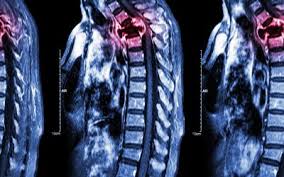

Metastatic Spine Tumors

Metastatic Spine Tumors from embed.widencdn.net

Imaging tests used for the diagnosis of bone metastases include: